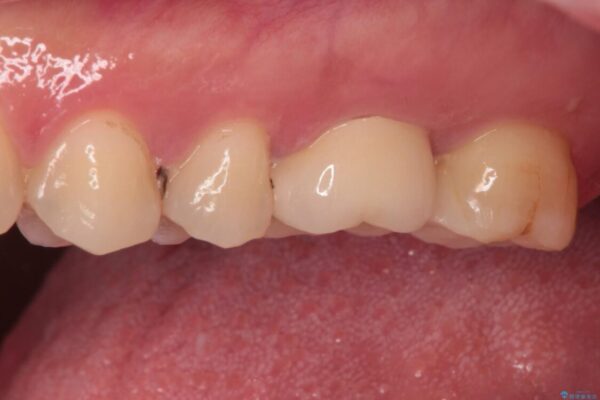

強い咬合力を負担する第一大臼歯であるため、根管治療後は速やかにオールセラミッククラウンにて補綴治療を行うこととしました。

治療後

• 奥歯がズキズキと痛む 奥歯の虫歯治療 治療後画像